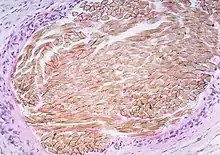

| Picture of a granuloma (without necrosis) as seen through a microscope on a glass slide: The tissue on the slide is stained with two standard dyes (hematoxylin: blue, eosin: pink) to make it visible. The granuloma in this picture was found in a lymph node of a patient with a Mycobacterium avium infection. | |

Granuloma without necrosis in a lymph node of a person with sarcoidosis